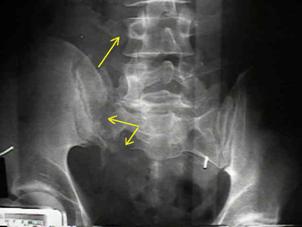

Rinichiul stang

Sistem

caliceal, ureter, vezica urinara ocupate de un cheag de sange

Lipsa vascularizatiei rinichiului stang Angiograma

Lipsa vascularizatiei rinichiului stang